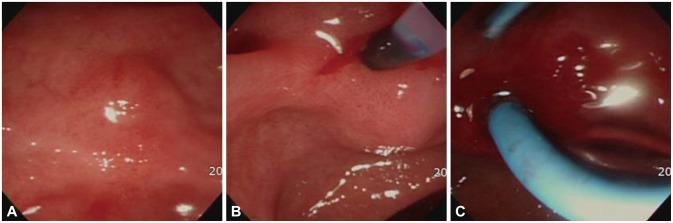

Acute pancreatitis due to a duodenal ulcer.

Duodenal ulcers and acute pancreatitis are two of the most commonly encountered gastrointestinal diseases among the general population. However, duodenal ulcer-induced pancreatitis is very rarely reported worldwide. This report elaborates on a distinct medical treatment that contributes to partial or complete treatment of acute pancreatitis induced by a duodenal ulcer scar.